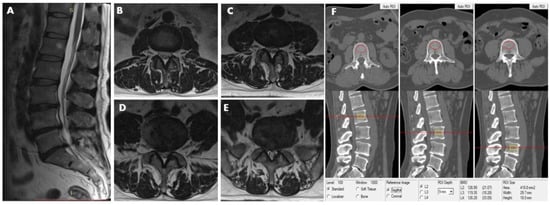

2.5. Lumbar Scanning by MRI

2.6. Definition of Lumbar Intervertebral Disc Herniation